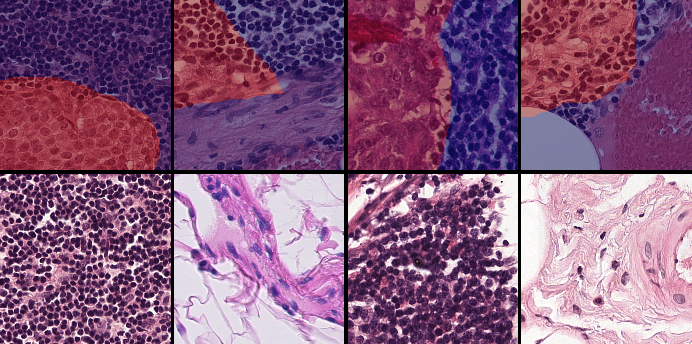

In this section, we describe the two public datasets of histology images used in our experiments: GlaS for colon cancer, and CAMELYON16 for breast cancer.

3.3.1 GlaS dataset (GlaS)

This is a histology dataset for colon cancer diagnosis (Sirinukunwattana et al., 2017)444The Gland Segmentation in Colon Histology Contest: https://warwick.ac.uk/fac/sci/dcs/research/tia/glascontest. It contains 165 images from 16 Hematoxylin and Eosin (H&E) histology sections and their corresponding labels. For each image, both pixel-level and image-level annotations for cancer grading (\ie, benign or malign) are provided. The whole dataset is split into training (67 samples), validation (18 samples), and testing (80 samples) subsets. Among the validation set, 3 samples per class are selected to be fully supervised, \ie, 6 samples in total for B-LOC selection.

3.3.2 Camelyon16 dataset (CAMELYON16)

This dataset555The Cancer Metastases in Lymph Nodes Challenge 2016 (CAMELLYON16): https://camelyon16.grand-challenge.org/Home is composed of 399 WSI for detection of metastases in H&E stained tissue sections of sentinel auxiliary lymph nodes (SNLs) of women with breast cancer (Ehteshami Bejnordi et al., 2017). The WSIs are annotated globally as normal or metastases. The WSIs with metastases are further annotated at the pixel level to indicate regions of tumors. An example of a WSI is provided in Figure 6. Among the 399 WSIs provided, 270 are used for training, and 129 for testing666Sample test_114 is discarded since the pixel level annotation was not provided. Therefore, the test set is composed of samples with samples with nodal metastases.. The large size of the images makes their use in this survey inconvenient. Therefore, we designed a concise protocol to sample small sub-images for WSL with pixel-wise and image-level annotations. In summary, we sample sub-images of size to form train, validation, and test sets, respectively (Fig.7). A detailed sampling protocol is provided in section B. This protocol generates a benchmark containing a total of 48,870 samples: 24,348 samples for training, 8,858 samples for validation, and 15,664 samples for testing. Each sub-set has balanced classes. For B-LOC, we randomly select 5 samples per class from the validation set to be fully supervised, \ie, 10 samples in total.